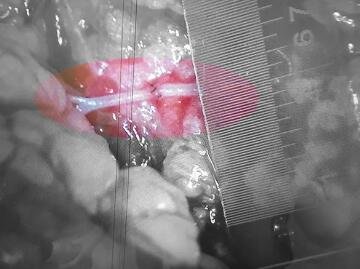

李甲主任介绍,萌萌这两场手术中,要将断开的血管、神经和肌腱重新连通,才能保证整个足跟的成活,以及未来的活动能力。“最细的一根血管只有0.4毫米,相当于要把两根头发丝头对头缝在一起。如果没有显微外科设备和熟练的技术,这种手术是无法进行的。”

▲手术中吻合血管最细处仅0.4毫米